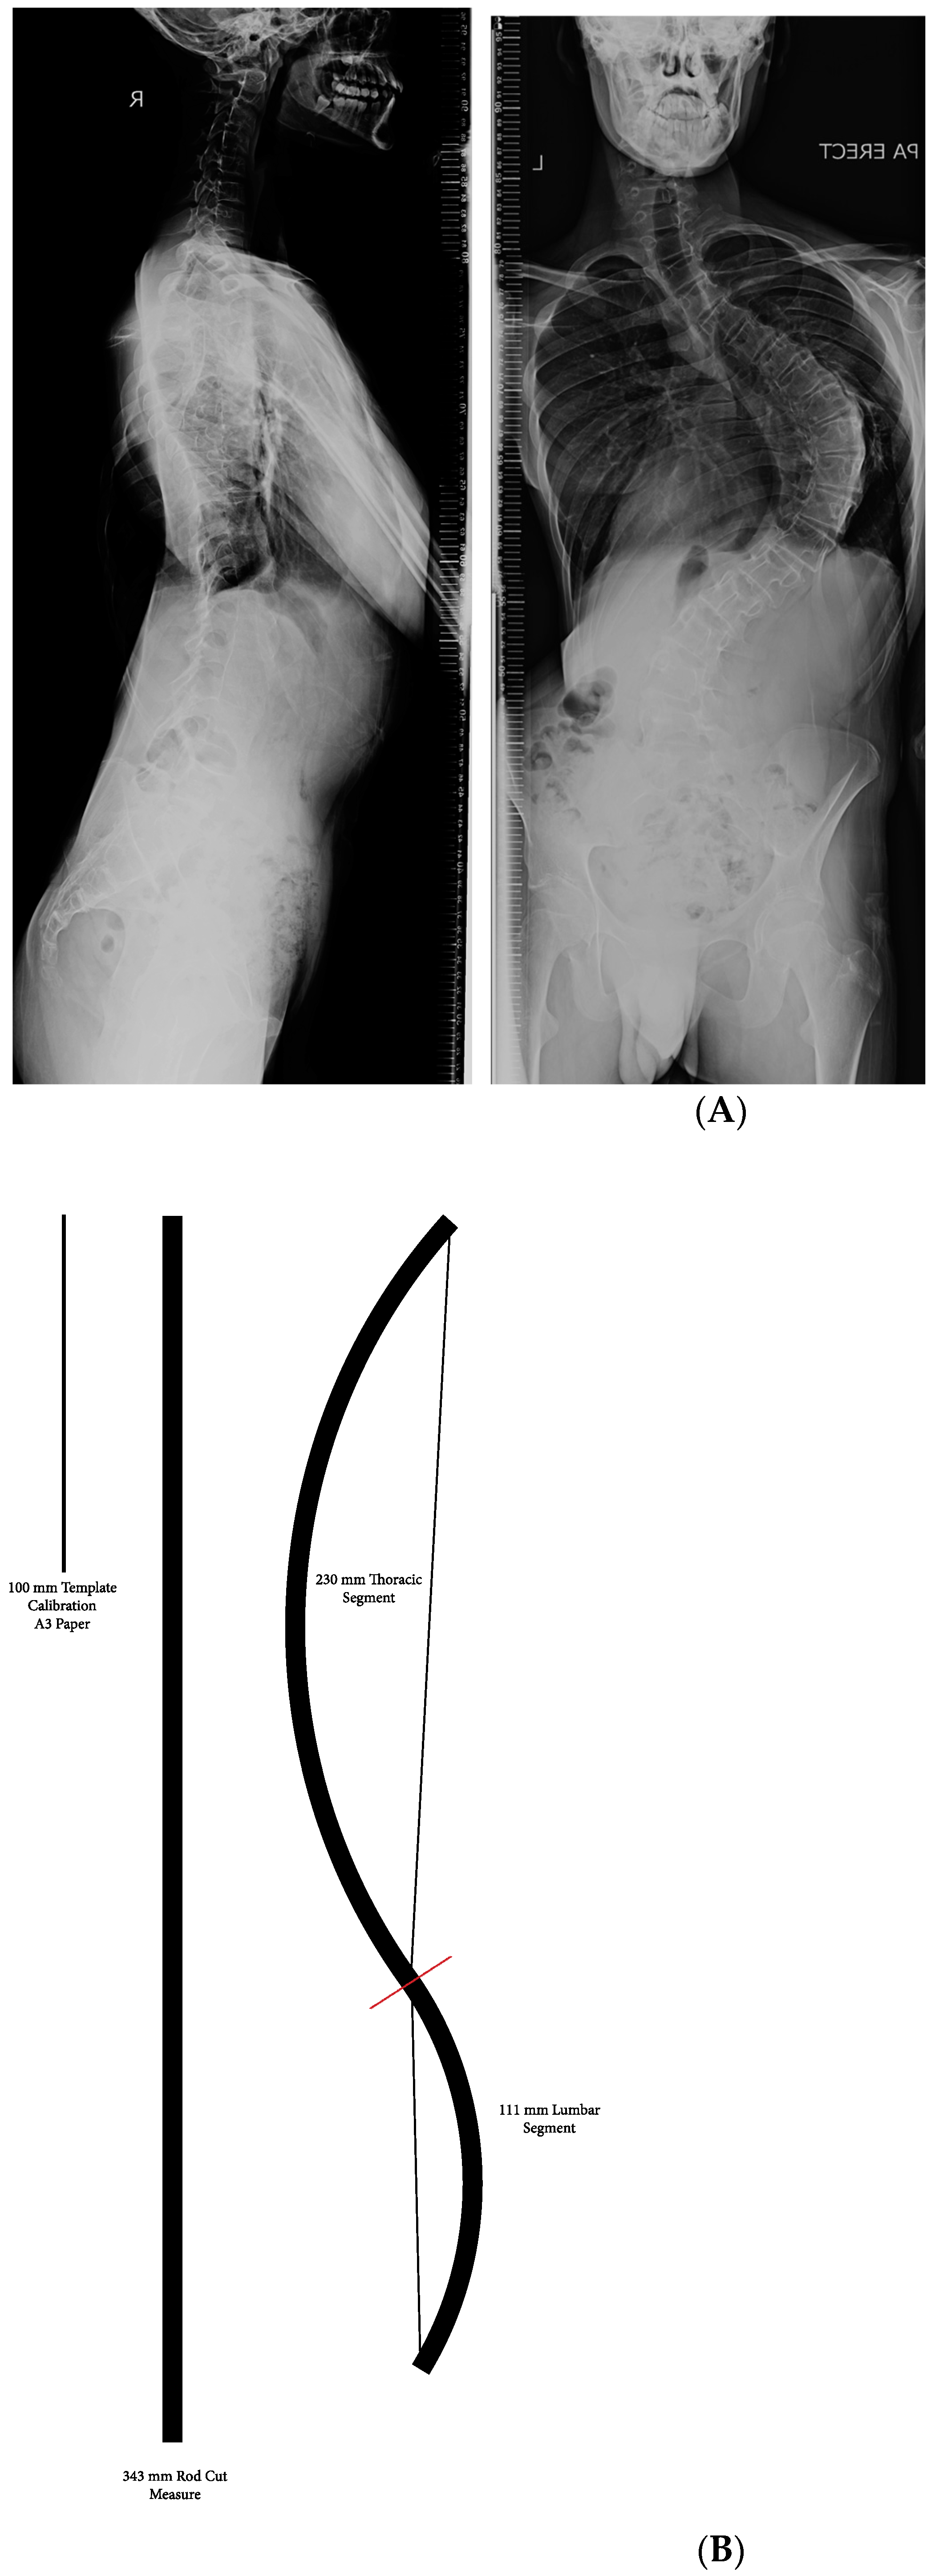

2. Materials and Methods